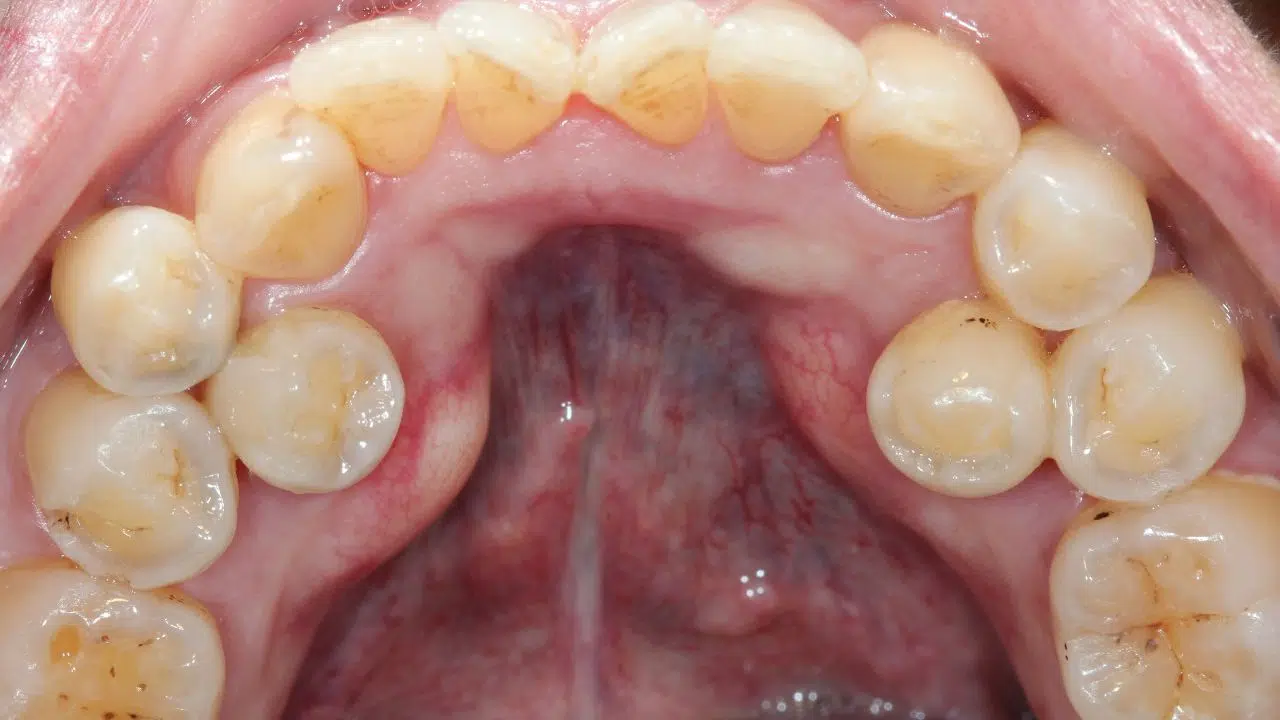

La prévalence de l’hyperdontie varie considérablement selon les populations étudiées. Globalement, elle affecte environ 1% à 2% de la population mondiale, avec une incidence légèrement plus élevée chez les hommes que chez les femmes. Les dents supernuméraires se trouvent le plus souvent dans la région maxillaire, particulièrement près des incisives.

Le diagnostic des dents supernuméraires se fait généralement par des examens radiographiques, tels que le panoramique dentaire, qui permet de visualiser l’ensemble de la denture. La détection précoce est cruciale pour prévenir les complications, telles que le déplacement des dents permanentes ou la surpopulation dentaire.

Les dents supernuméraires peuvent entraîner diverses complications, notamment des problèmes d’alignement et de malocclusion. Dans certains cas, elles peuvent rester incluses (non éruptées dans la gencive), nécessitant une intervention chirurgicale. Le traitement varie selon les cas, allant de l’ablation chirurgicale à l’orthodontie corrective post-opératoire.